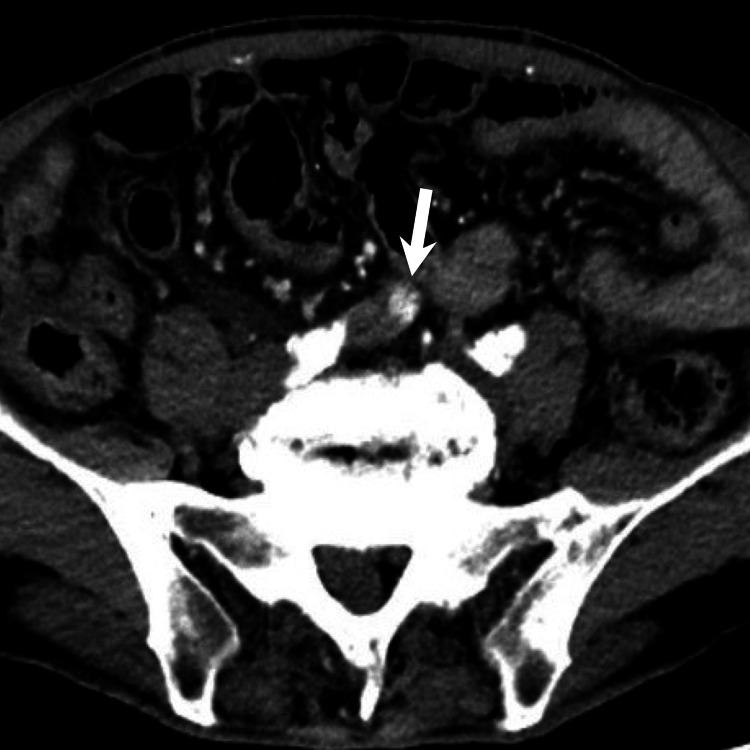

Small bowel arteriovenous malformation (AVM) is a rare vascular lesion, which should be considered in patients presenting with gastrointestinal bleeding, as it is a high-flow arterial lesion that can cause life-threatening bleeding. Although a primary endoscopic examination is performed in cases of suspected small bowel bleeding, the diagnosis of the causal lesion is sometimes difficult. We are presenting a case of small bowel AVM that could not be diagnosed endoscopically but was successfully detected using multiphase CT images with an appropriate protocol. The AVM diagnosis was confirmed using digital subtraction angiography. An endovascular coil is placed in the draining vein as a surgical resection marker. The AVM was resected successfully without any complications.

小肠动静脉畸形(AVM)是一种罕见的血管病变,对于出现胃肠道出血的患者应考虑到这种病变,因为它是一种高流量动脉病变,可导致危及生命的出血。尽管在疑似小肠出血的病例中会进行初步内镜检查,但有时很难诊断出病因性病变。我们现报告一例小肠AVM,内镜检查未能诊断出来,但通过采用适当方案的多期CT图像成功检测到了该病变。通过数字减影血管造影术确诊为AVM。在引流静脉中放置了一个血管内线圈作为手术切除标记物。成功切除了AVM,未出现任何并发症。